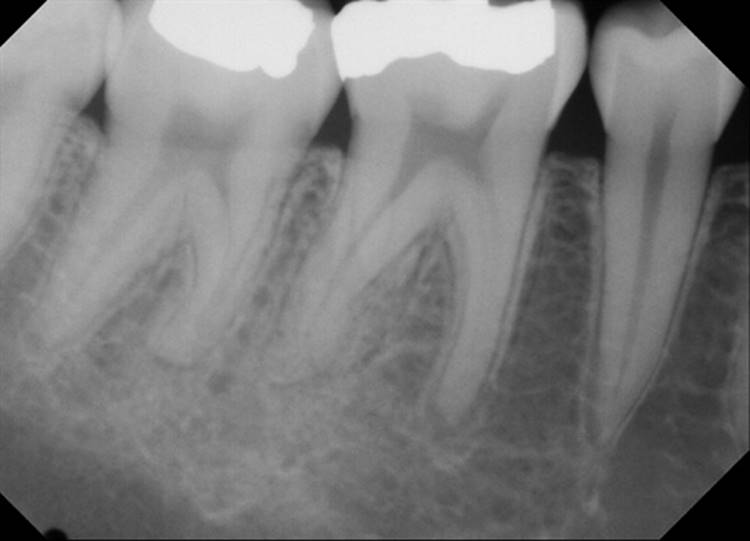

Forgive the sensor change from the first two cases to the last two. The good sensor broke and the back up isn’t as great.

EdgeFile® Cases